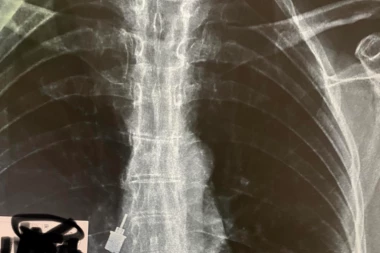

Beograd 10:59 02.08.2022 DRAMA! Popravljao ženi zub, pa mu ovo ispalo! Hitno primljena u Urgentni centar! (FOTO)